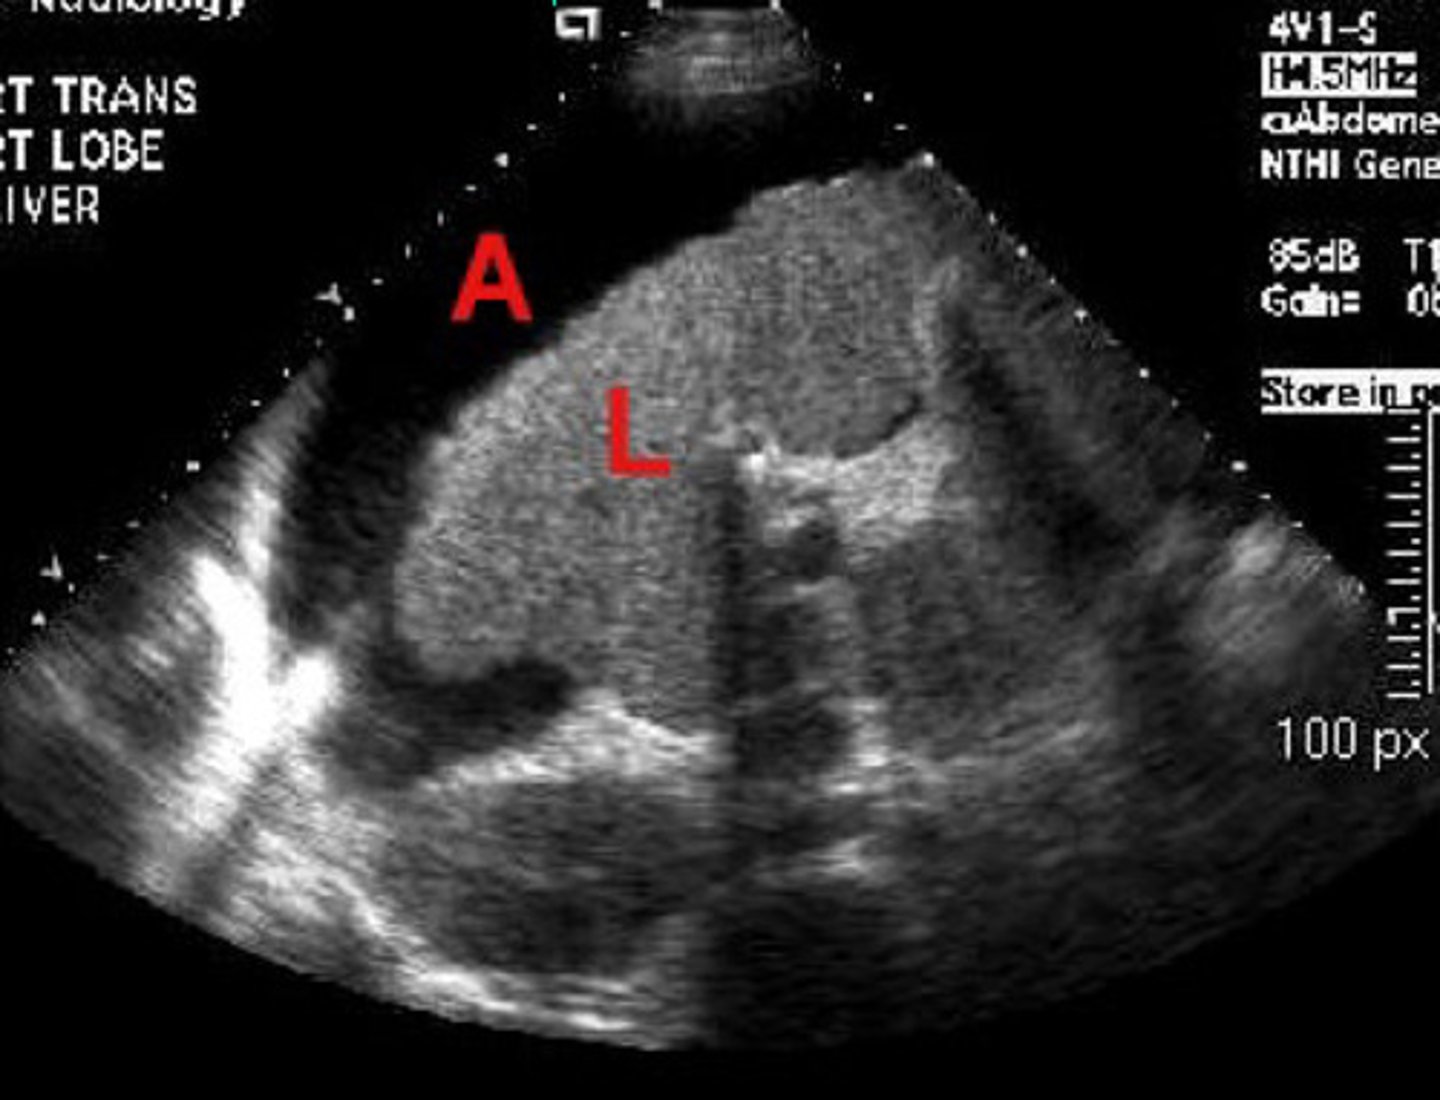

Abnormal = small irregularly marginated liver at L and ascites at A = chronic hepatitis and scar tissue present

What is going on here? Is this normal or abnormal?